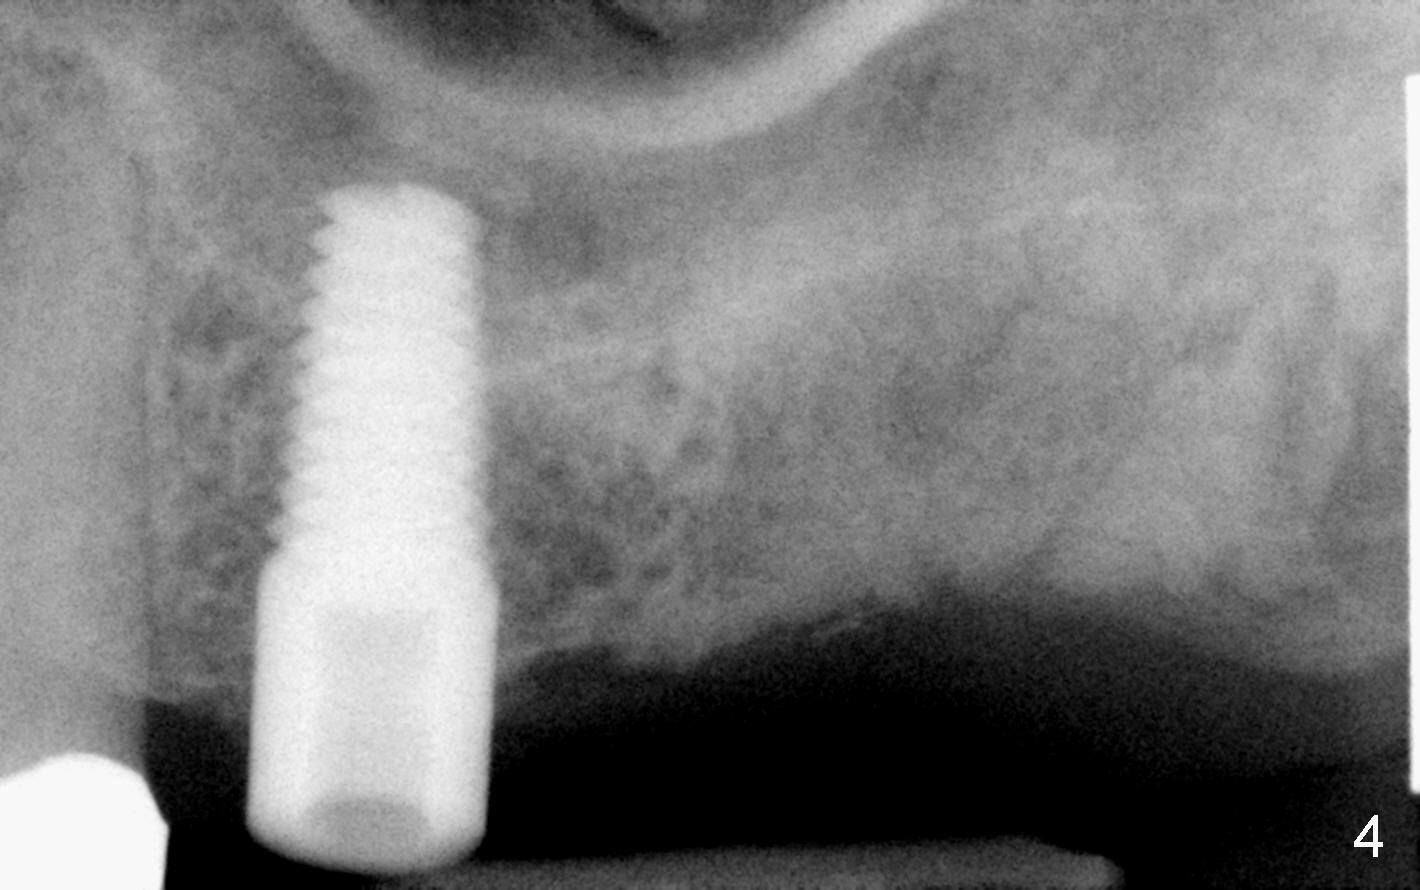

Fig.2 shows a 1.6 mm pilot drill at the depth of 11 mm; the tip of the drill penetrates the sinus floor. Bone expanders (2.6, 3.0, 3.4, 3.8 (Fig.3) and 4.3 mm) are used and alternated with tapered osteotomes (3 and 4 mm). The latter are used to break through the sinus floor. Then 4.5x14 mm and 5x14 mm taps are applied to create threads for implant. The second tap has some binding to the bone. Finally 5x14 mm tapered implant is inserted with more than 60 Ncm torque (Fig.4). Although the apical portion of implant (approximately 3 mm) pokes into the sinus, the patient does not experience nasal hemorrhage intra- or post-op.